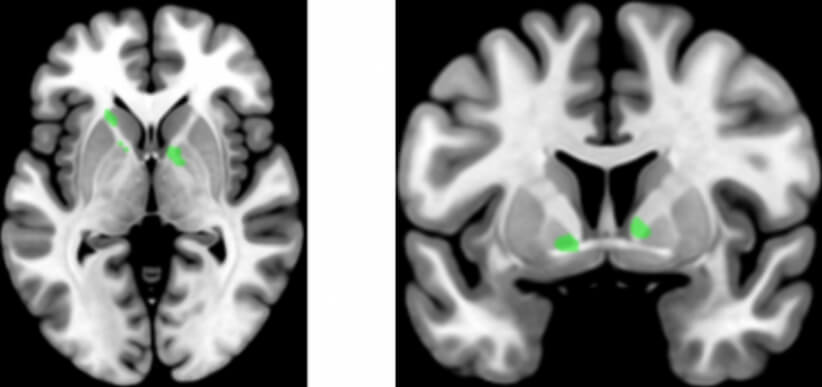

В статье, опубликованной в журнале Science, сотрудники Inserm рассказывают о новом своем исследовании, цель которого состояла в том, чтобы выяснить, какие участки мозга отвечают за моторику рук и речь. Для этого авторы работы проверяли умение добровольцев обращаться с плоскогубцами, а также знание грамматики. При этом они следили за активностью мозга добровольцев при помощи магнитно-резонансной томографии. Это позволило визуально определить какие части мозга были активны при выполнении тех или иных задач.

В результате ученым впервые удалось выяснить, что существует участок мозга, который активен и во время языковых упражнений, и при выполнении мелких, сложных действий руками. Он расположен в ганглиях. Другими словами, один и тот же участок мозга отвечает за разные задачи. Выяснив это, исследователи задались другим вопросом — можно ли путем тренировки мелкой моторикой рук выявленного участка мозга улучшить языковые способности человека?